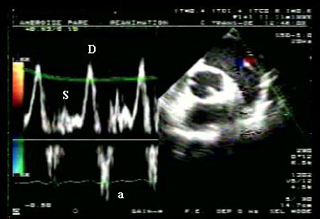

Figure 3 : ETO coupe grand axe du VG chez un patient ventilé pour un OAP cardiogénique en rapport avec une myocardique. Doppler pulsé au niveau de l'anneau mitral. LV : ventricule gauche, RV : ventricule droit, LA : oreillette gauche. E : remplissage rapide protodiastolique du VG. A : remplissage télédiastolique du VG (systole auriculaire). Aspect restrictif du flux mitral (E/A > 2, temps de décélération de l'onde E bref), évocateur d'une pression télédiastolique du ventricule gauche élevée

Figure 4 : Coupe ETO passant par la veine pulmonaire supérieure gauche chez le même patient qu'à la figure 3. S : onde systolique, D : onde diastolique. a : onde rétrograde contemporaine de la systole auriculaire. L'aspect inversé du flux de remplissage de l'oreillette gauche (petite onde systolique, grande onde diastolique), ainsi que la présence d'une onde a significative, sont évocateurs d'une pression télédiastolique du VG élevée.